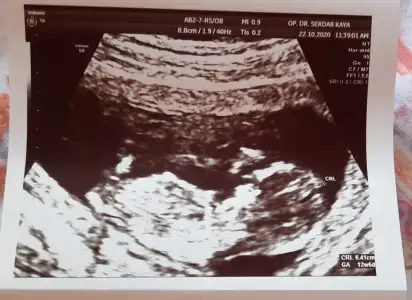

Merhaba Ikra meyra Ikra meyra canım, bir tahmin alabilir miyim ben de 13+2 olduk. :KK36:

Eklentiler

• 20201021_114201.webp

20201021_114201.webp

23,3 KB · Görüntüleme: 63

• 20201021_114209.webp

20201021_114209.webp

23,7 KB · Görüntüleme: 51

• 20201021_114216.webp

20201021_114216.webp

18,4 KB · Görüntüleme: 80